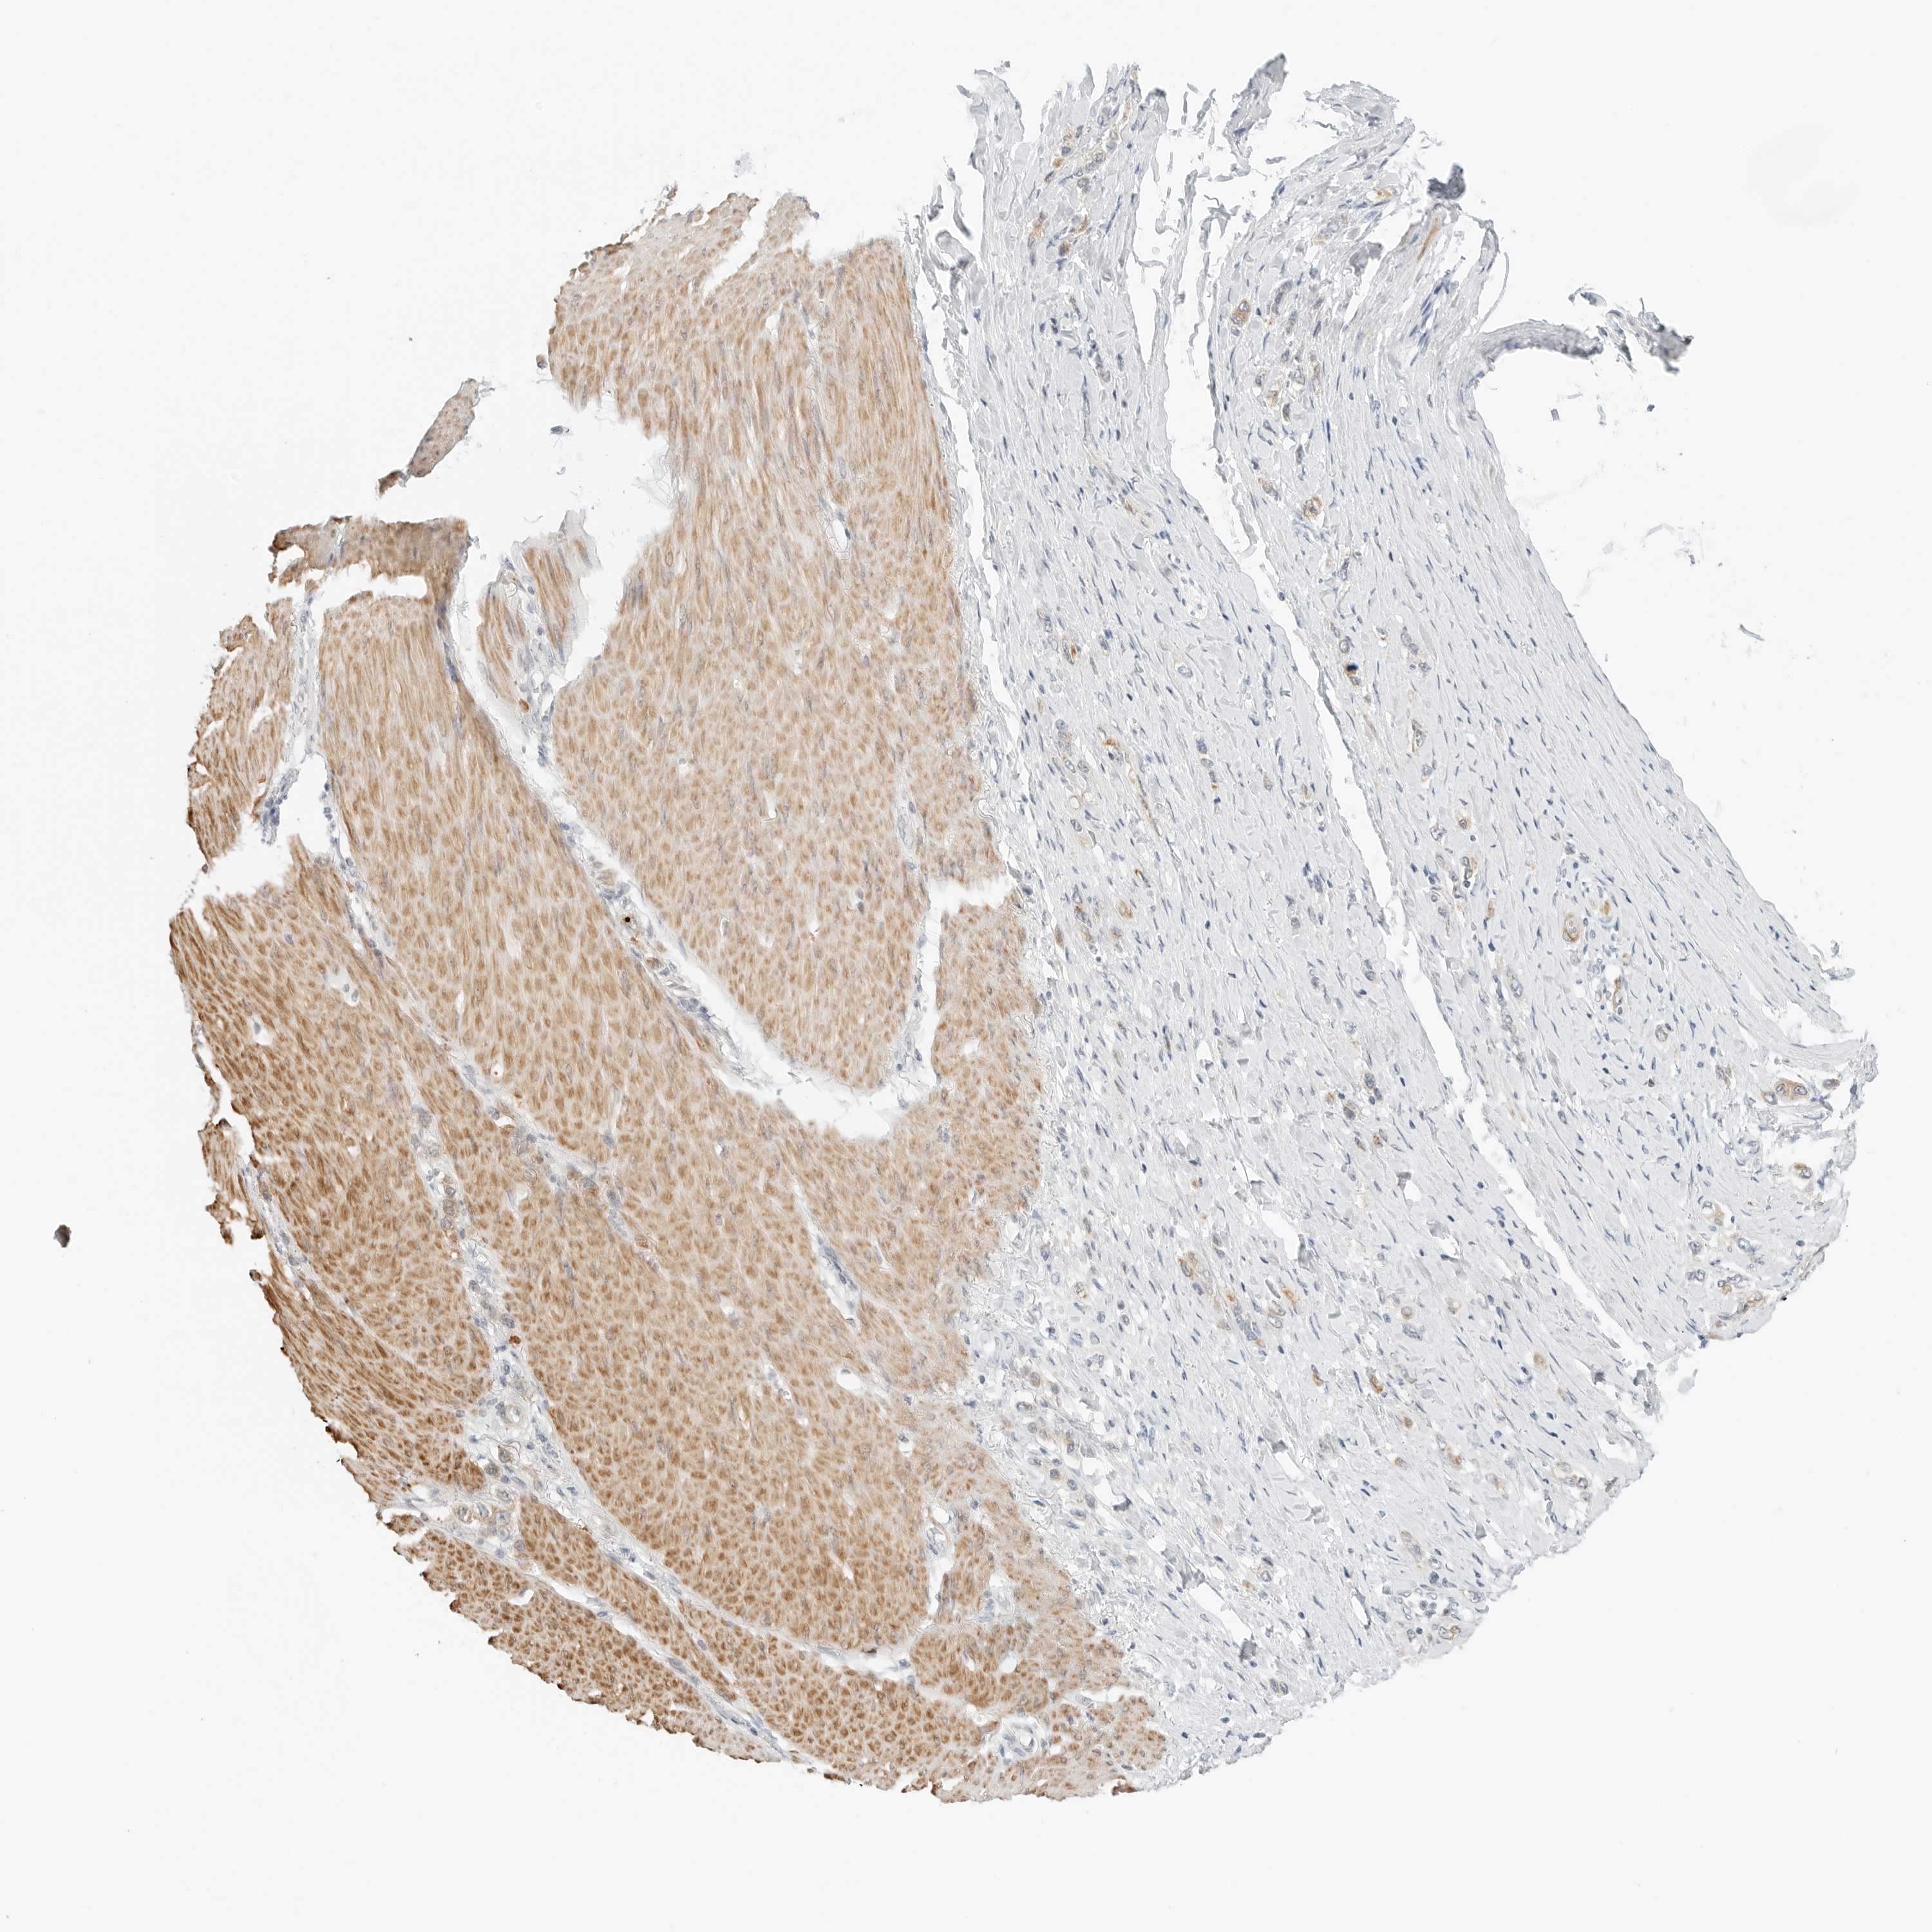

STOMACH CANCER - Protein expressioni

A mouse-over function shows sample information and annotation data. Click on an image to view it in a full screen mode. Samples can be filtered based on level of antibody staining by selecting one or several of the following categories: high, medium, low and not detected. The assay and annotation is described here.

Antibody stainingi

Antibody staining in the annotated cell types in the current human tissue is reported as not detected, low, medium, or high, based on conventional immunohistochemistry profiling in selected tissues. This score is based on the combination of the staining intensity and fraction of stained cells.

Each image is clickable and will lead to virtual microscopy that enables deeper exploration of all samples and also displays staining intensity scores, fraction scores and subcellular localization as well as patient and tissue information for each sample.

Antibody HPA028602

Antibody HPA028686

Adenocarcinoma, NOS